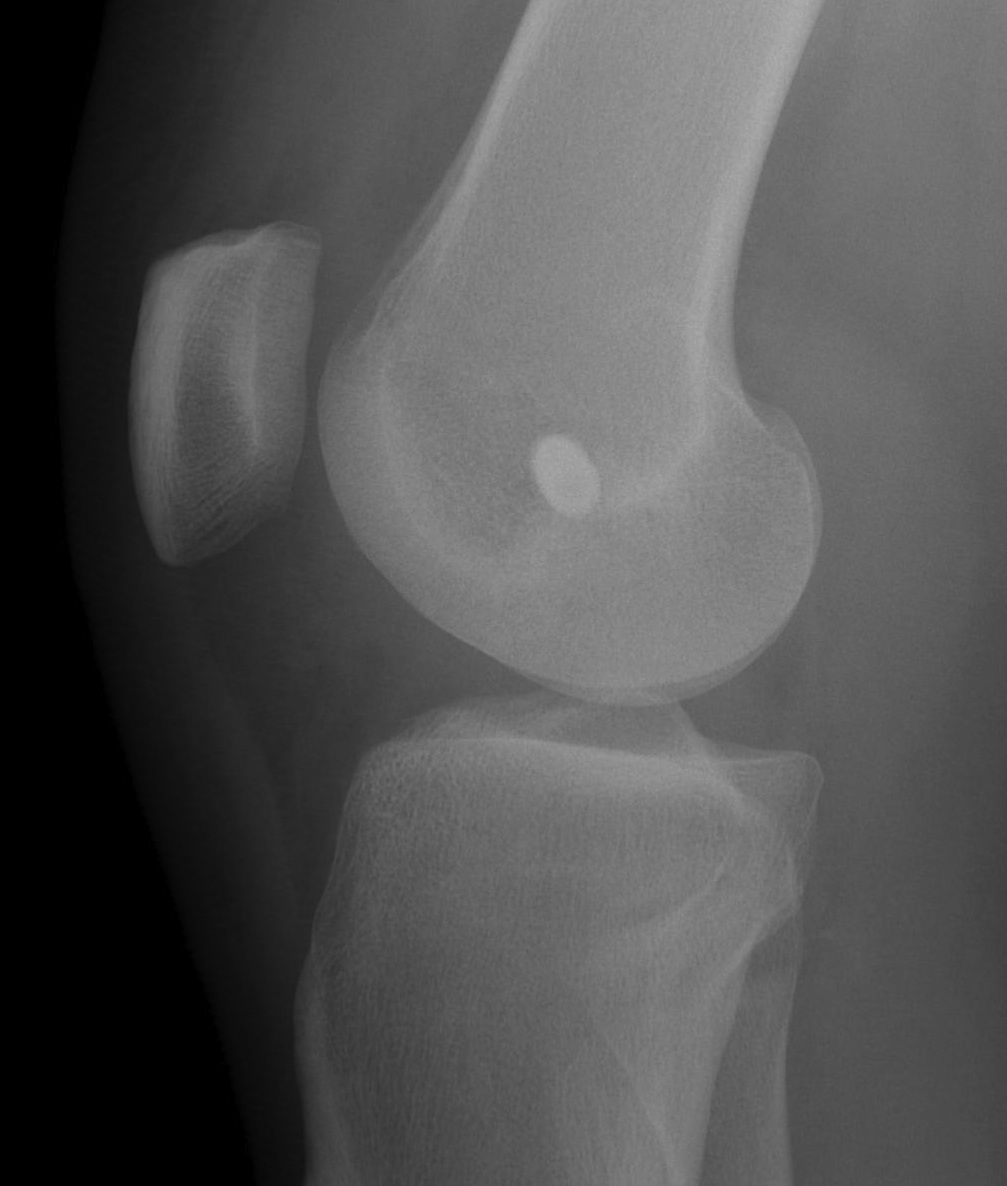

Left knee with LCL and popliteus tunnels and screw fixation of grafts